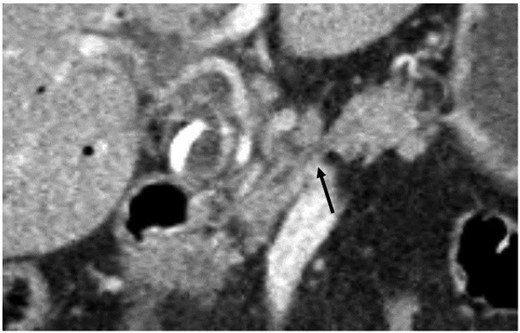

A 78-year-old woman with metabolic syndrome and chronic obstructive pulmonary disease developed obstructive jaundice and underwent endoscopic biliary stenting and papillotomy for suspected periampullar carcinoma (double-pigtail endoprothesis, 10 Fr./7 cm). Histology revealed a moderately differentiated bile duct carcinoma. Cytopathology showed a class V PAP stain with adenocarcinoma cells. The abdominal computed tomography displayed an inhomogenous hypodense tumor in the pancreatic head of 2 cm diameter with no signs of metastatic spread. The proximal part of the pancreatic corpus seemed to be atrophic (see Fig. 1). Endosonography demonstrated a tumor of the ampulla of Vater with a size of 20 × 23 mm and infiltration of the duodenal wall (at least uT2uN1).

Coronary abdominal CT scan: missing pancreatic isthmus with isolated pancreatic duct (arrow).

The pancreatic isthmus links with a thin layer of parenchyma head and body of the pancreas, however, unusual contours or areas of fatty replacement can mimick a neoplasm [8]. In the preoperative computed tomography an atrophic or missing proximal part of the pancreatic body was suspected and identified as a missing neck during surgery.